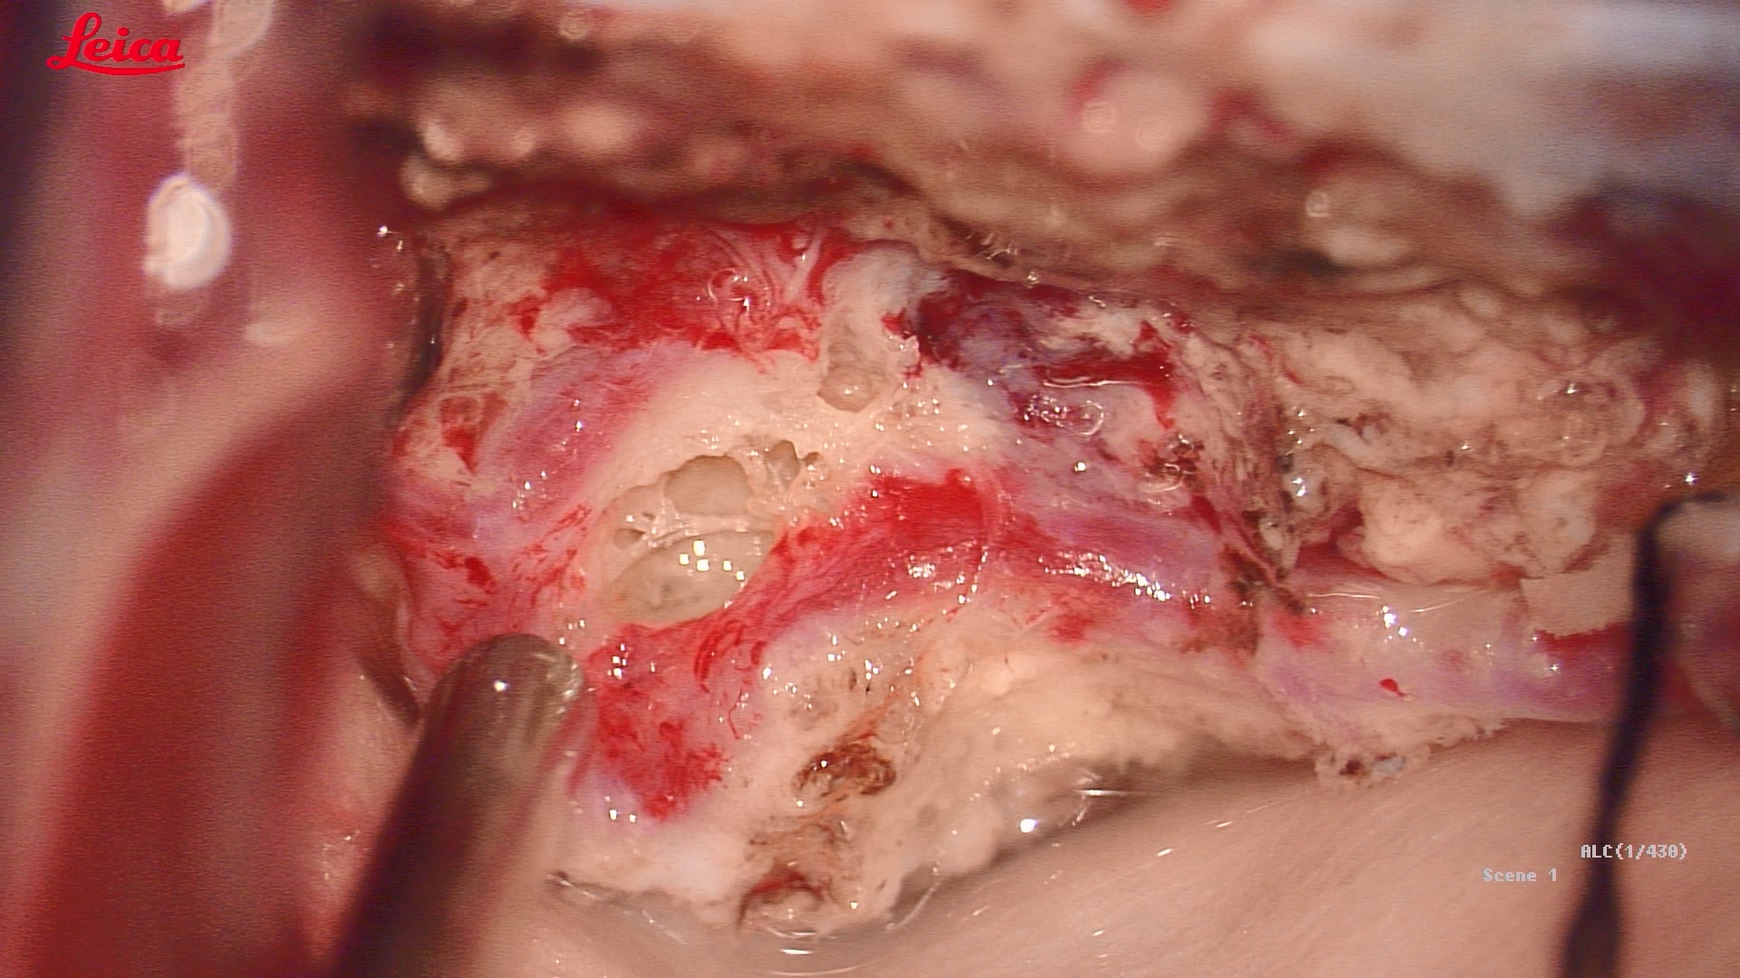

巨大蝴蝶型胶质母细胞瘤(Butterfly glioblastomas)切除术

患者,女性,58岁,因“反应迟钝、记忆力下降1月,加重伴头痛、恶心、呕吐1周”入院。

术后第二天,患者症状显著改善,认知功能明显好转

术后半月恢复正常生活